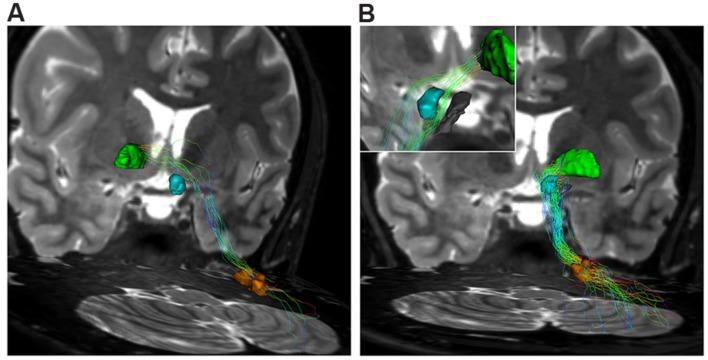

The connections between the cerebellum and basal ganglia were assumed to occur at the level of neocortex. However evidences from animal data have challenged this old perspective showing extensive subcortical pathways linking the cerebellum with the basal ganglia. Here we tested the hypothesis if these connections also exist between the cerebellum and basal ganglia in the human brain by using diffusion magnetic resonance imaging and tractography. Fifteen healthy subjects were analyzed by using constrained spherical deconvolution technique obtained with a 3T magnetic resonance imaging scanner. We found extensive connections running between the subthalamic nucleus and cerebellar cortex and, as novel result, we demonstrated a direct route linking the dentate nucleus to the internal globus pallidus as well as to the substantia nigra. These findings may open a new scenario on the interpretation of basal ganglia disorders.

小脑与基底神经节之间的连接曾被认为发生在新皮层水平。然而,动物数据的证据对这一旧观点提出了挑战,显示出连接小脑与基底神经节的广泛皮质下通路。在这里,我们通过使用扩散磁共振成像和纤维束成像技术,测试了人类大脑中小脑与基底神经节之间是否也存在这些连接的假设。对15名健康受试者使用3T磁共振成像扫描仪获得的约束球形反卷积技术进行分析。我们发现丘脑底核与小脑皮质之间存在广泛连接,并且作为新的结果,我们证明了一条将齿状核与苍白球内部以及黑质相连的直接路径。这些发现可能为基底神经节疾病的解释开辟一个新的局面。